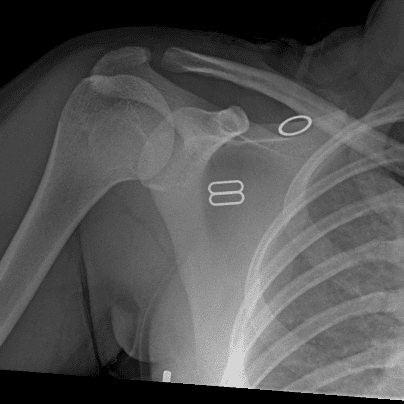

Simuliert den Dienst durch subtile oder schwierige Fälle und einige Normalbefunde.

30 Fälle